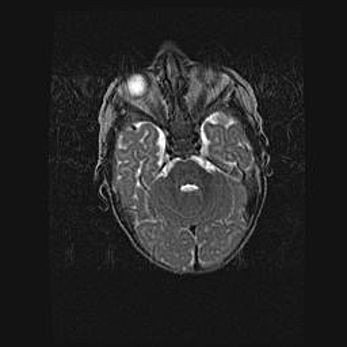

Множественные кисты обоих полушарий головного мозга, наибольшая из них в правой затылочной области. Ассиметричная атрофическая гидроцефалия.

Возраст: 7 месяцев

Вес: 5660 г

Пол: мужской

Окружность головы: 41,5 см

Срок гестации: 28-29 недель

Кисты головного мозга развиваются в результате многоочаговых некрозов вещества мозга и возникают вследствие перенесенной перинатальной инфекции, менингитов, энцефалитов, асфиксии, родовой травмы, расстройств мозгового кровообращения различного генеза. Образованию кист в веществе головного мозга плодов и новорожденных способствуют такие факторы, как высокое содержание в нем воды, недостаточная (или отсутствие) миелинизация и слабая астроглиальная реакция на повреждение.

Кисты могут сочетаться с гидроцефалией и другими поражениями головного мозга.